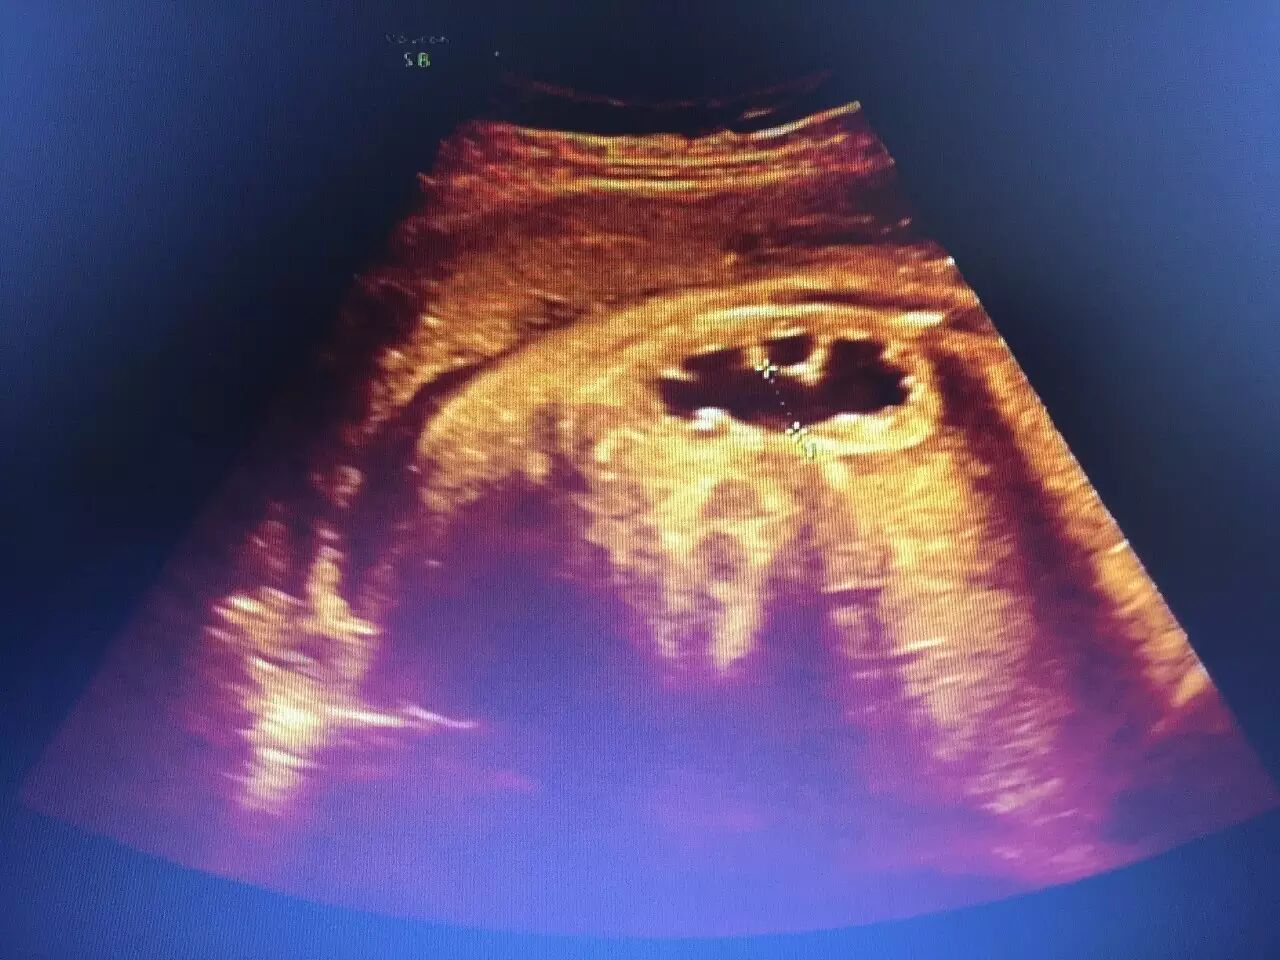

(上图为胎儿肾积水)